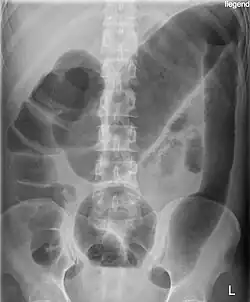

Toxic megacolon in a patient with ulcerative colitis: The patient subsequently underwent a colectomy.

Massively dilated colon with air-fluid level can be seen on abdominal radiograph or CT scan.[7][8]

To diagnose toxic megacolon (TM), the criteria include: (a) radiographic evidence of the colon being dilated to over 6 cm, especially in the transverse colon; (b) at least three of the following symptoms: fever (over 38.6°C), rapid heartbeat (over 120 beats per minute), high white blood cell count (over 10.5 × 10³/μL), or anemia; and (c) signs of severe illness like low blood pressure, dehydration, confusion, or electrolyte imbalances.[9]

Imaging, particularly CT scans, is crucial for diagnosis and to check for complications that may need immediate surgery. X-rays are used to track the size of the colon. Common imaging findings include dilation of the transverse or right colon, mucosal ulcers, thinning of the colon wall, air-fluid levels, and pseudopolyps. Blood tests typically show high white blood cells, anemia from blood loss, metabolic alkalosis, low potassium, low albumin, and elevated markers of inflammation.[9]